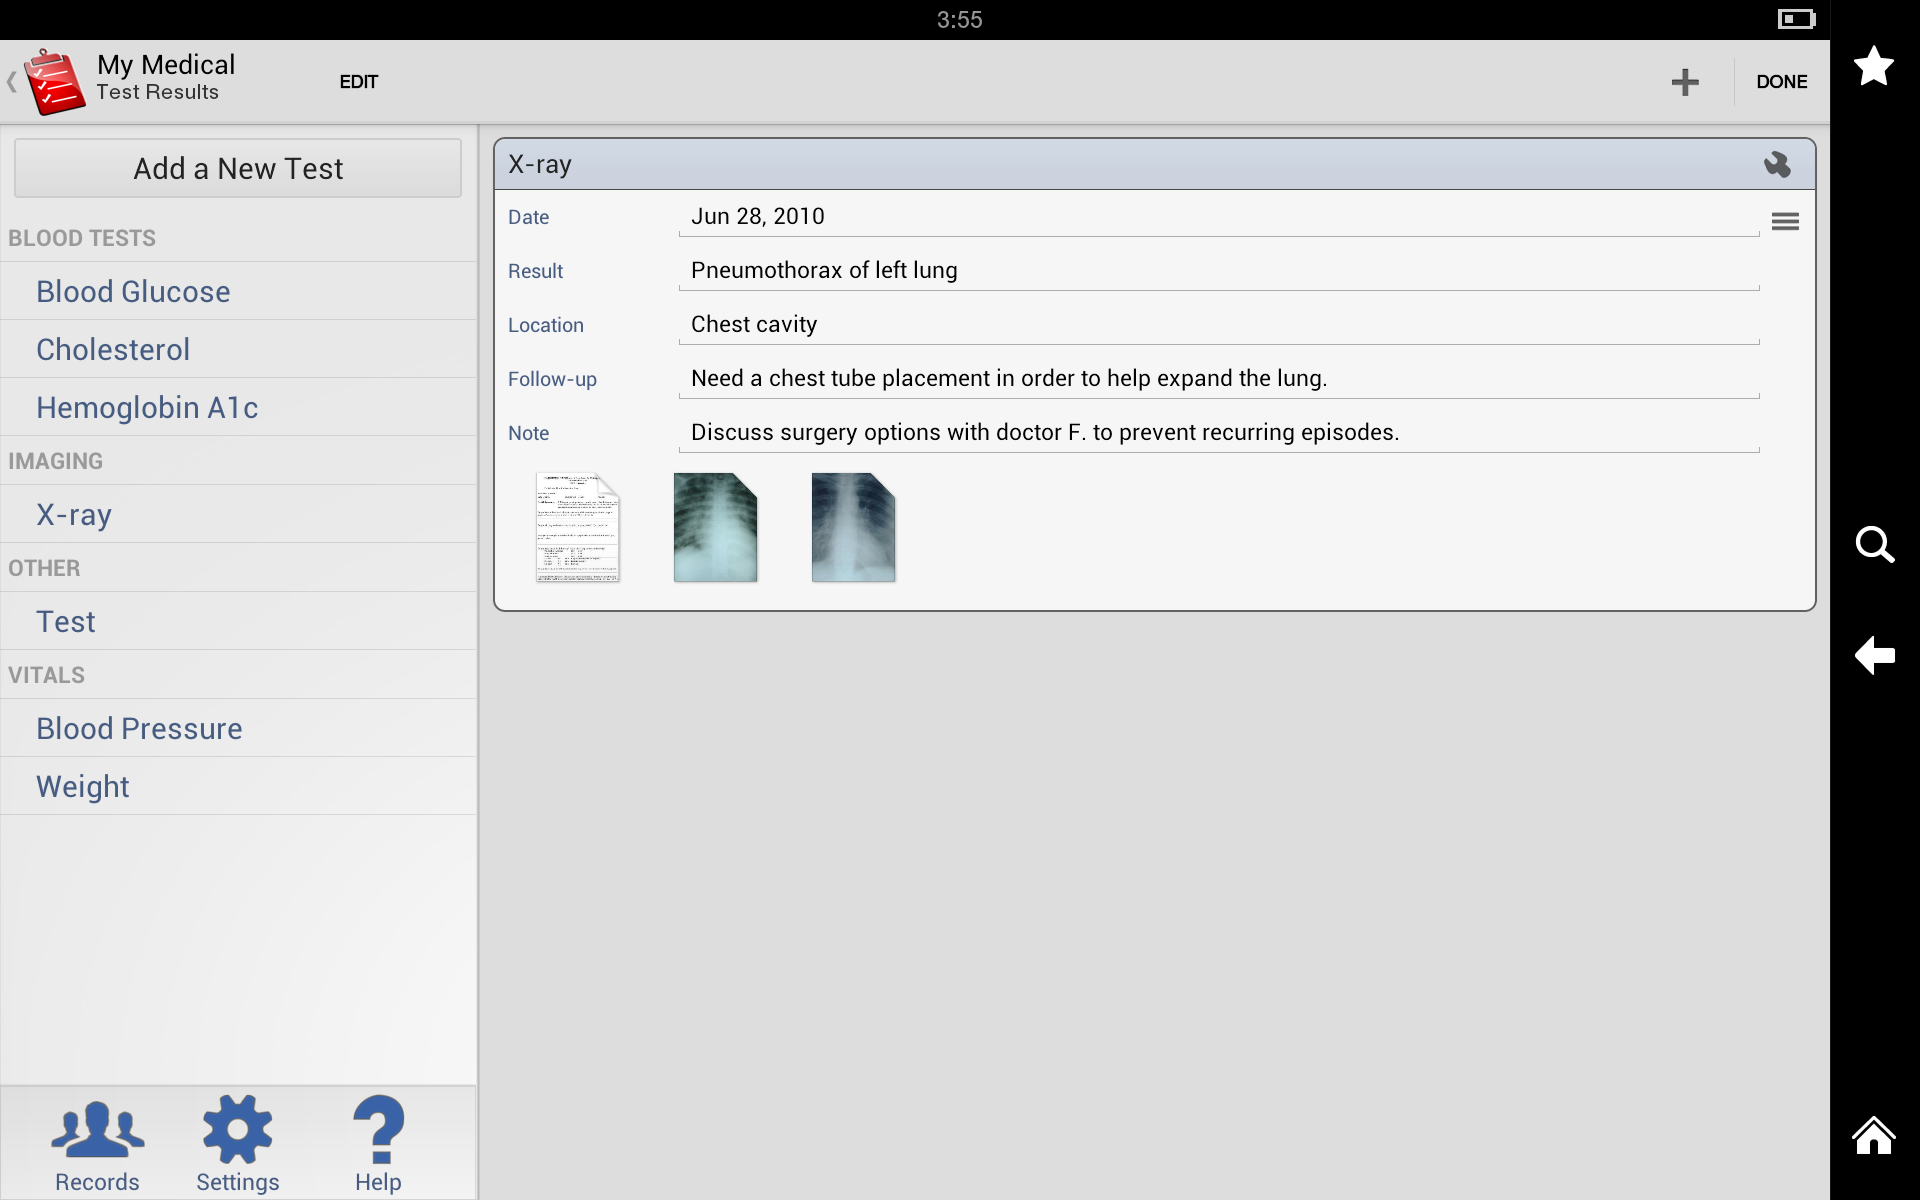

Test Results

My Medical allows you to store and track the results of medical tests such as blood work, x-rays, and MRIs. You can also add notes to provide context for the results.

My Medical allows you to store and track the results of medical tests such as blood work, x-rays, and MRIs. You can also add notes to provide context for the results.

User Interface

My Medical has a clean, intuitive interface that makes it easy to navigate and use. The app is organized into tabs for each section, making it easy to find the information you’re looking for. The buttons and menus are clearly labeled, and the app uses intuitive icons to represent different functions.